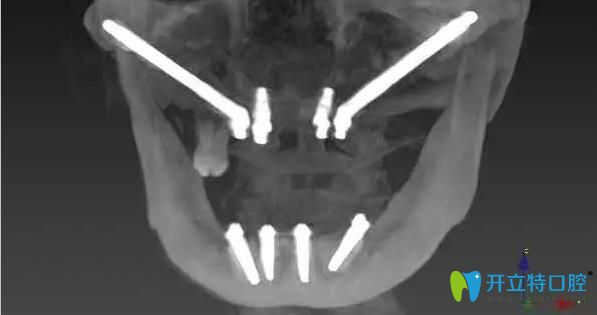

林阿姨,68歲,上下牙缺失多年,牙槽骨大量缺失,上頜竇氣化非常嚴(yán)重,前牙區(qū)的骨骼也特別窄、矮,做任何的修復(fù)都很困難,所以陳慧玲院長(zhǎng)建議她做穿顴骨種植。

什么是穿顴骨種植牙——穿顴種植是利用植體的一端穿過顴骨,另一端平臺(tái)放置在盡可能接近牙槽嵴頂?shù)奈恢茫尫N植體有一個(gè)45°的轉(zhuǎn)角基臺(tái),獲得的咬合力,主要由顴骨支撐,從而在牙頜骨缺失的情況下,不植骨也可以進(jìn)行種植牙修復(fù)。此項(xiàng)技術(shù)目前在國(guó)內(nèi)外都屬于是前沿技術(shù)。

陳慧玲院長(zhǎng)經(jīng)過詳細(xì)的術(shù)前檢查、做了充分的種植手術(shù)評(píng)估后,確定了種植方案。在多名醫(yī)生的共同努力下,利用穿顴種植+穿翼種植技術(shù),用六顆種植體來進(jìn)行上半口全固定修復(fù),即刻種植、即刻修復(fù)。當(dāng)天下午,林阿姨就戴上了固定臨時(shí)牙,回家就可以吃東西。